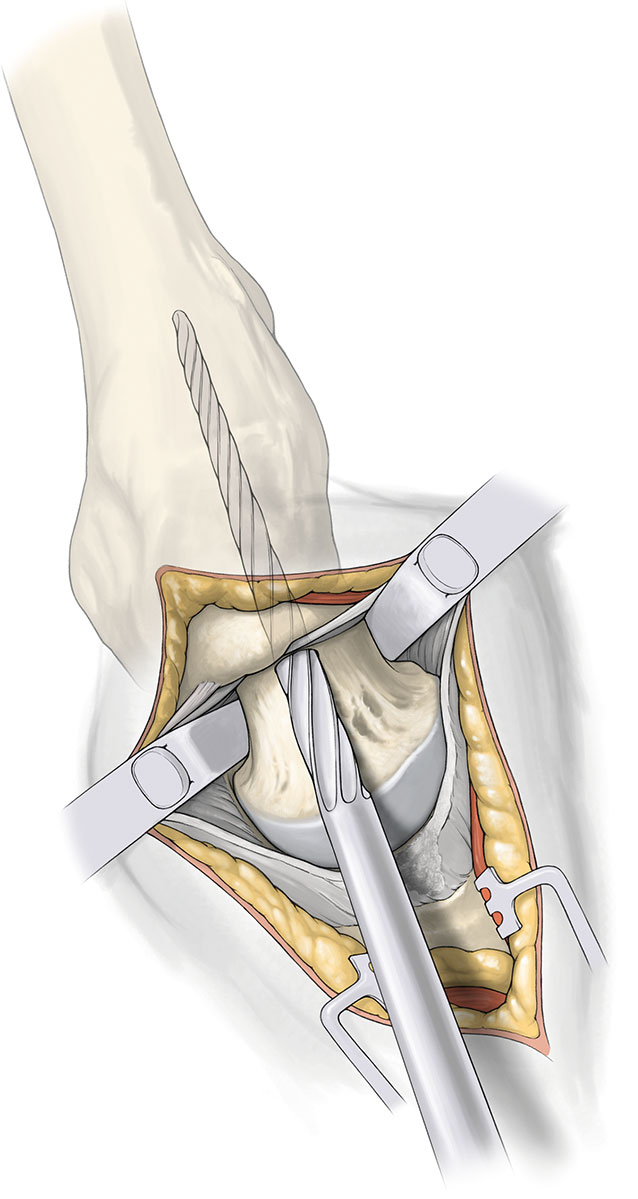

用带手柄的斯氏针插入股骨头的硬质部分,最大程度旋转并内收股骨头,或辅助另一根斯氏针取出股骨头。